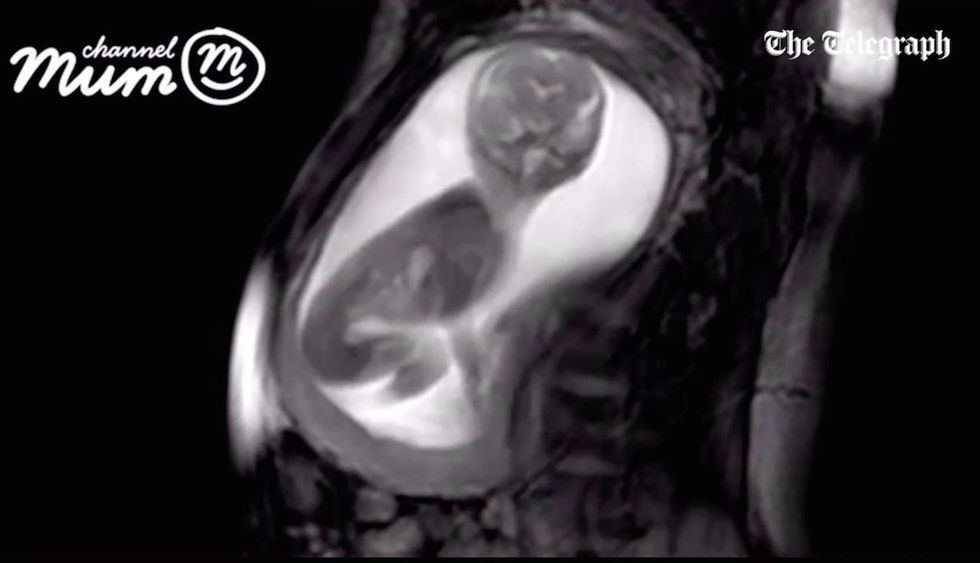

Image source: The Telegraph

A group of researchers have captured the clearest images of an unborn baby in the womb ever taken, according to The Telegraph.

The international team of researchers at the iFIND project captured footage of a baby at 20 weeks gestation using new computer-guided ultrasound technologies.

The baby, the child of an unnamed mother in London, can be seen in the video moving its umbilical cord, moving its head from side to side and stretching and kicking in the mother’s womb.